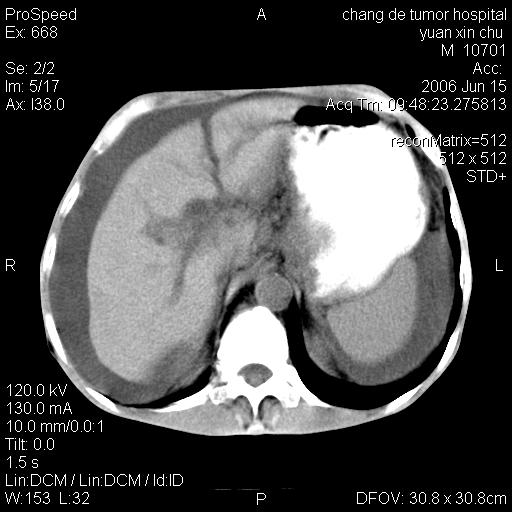

以下是引用qian在2007-4-23 19:06:00的发言:[br]胰腺体积增大,轮廓欠规则,肝轮廓波浪状改变,肝裂增宽,肝周、脾周有液性密度,腹膜后肿大淋巴结,考虑1、胰腺癌伴腹膜后淋巴结转移;2、肝硬化伴腹水。

以下是引用卜一在2007-4-23 20:12:00的发言:[br]胰腺体积增大,轮廓欠规则,肝轮廓波浪状改变,肝裂增宽,肝周、脾周有液性密度,腹膜后肿大淋巴结,考虑1、胰腺癌伴腹膜后淋巴结转移;2、肝硬化伴腹水。支持!